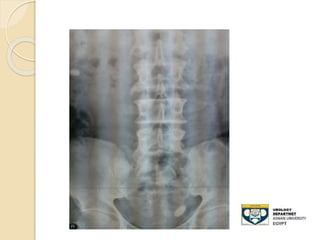

STONE UPPER THIRD URETER